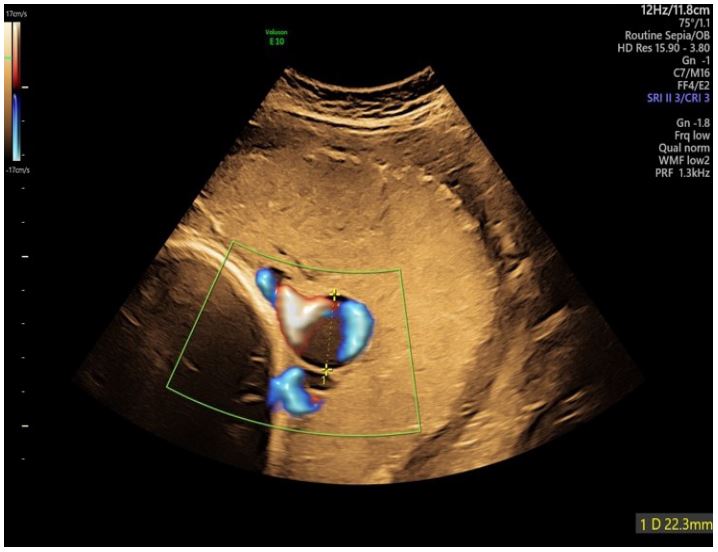

On our first ultrasound examination we discovered the varix of the umbilical vein right at the placenta insertion site. The widest diameter was 22 mm (Figure 1).

Figure 1: Transabdominal 2D ultrasound using color doppler (transverse view) at 39 weeks showing a dilated umbilical vein on the surface of the placenta.